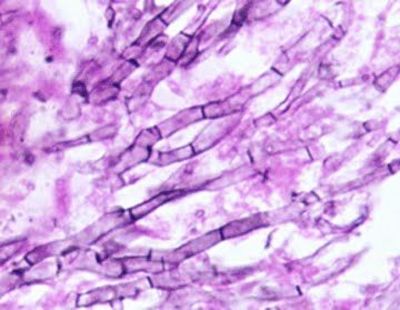

What is the mold pictured?

Answer

• Aspergillis

• Penicillium

• Rhizopus

Question

• Aspergillus

Question 70